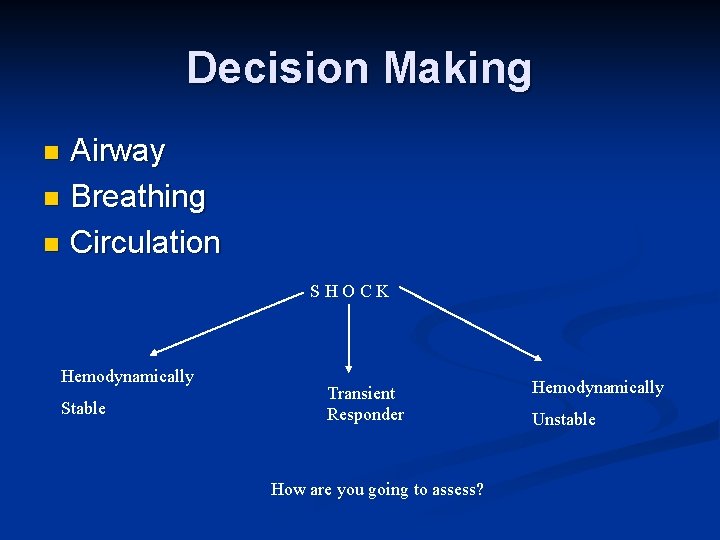

Decision Making Airway n Breathing n Circulation n SHOCK Hemodynamically Stable Transient Responder How are you going to assess? Hemodynamically Unstable

Shock Scalp n Chest – clinically vs. chest x-ray n Abdomen n FAST n DPL n Pelvic X-ray n Extremities – Femur n Other causes of shock – cardiogenic, obstructive, anaphylactic, septic n